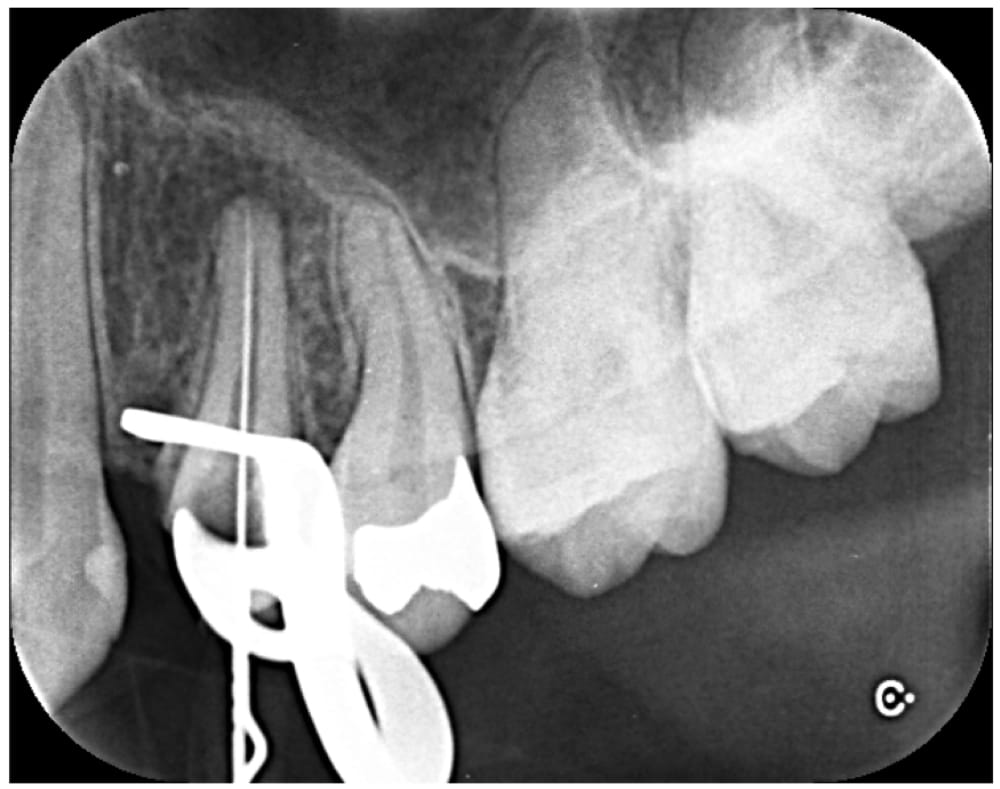

金属製のスクリューポストが入っていたため、残存歯質に負担がかからないように超音波の振動で除去を行いました。比較的シンプルな根管形態であったため、治療は1回で完了し、ファイバーポストを併用してラバーダム防湿下でコア築造まで行いました。

| 根管充填 | バイオセラミックシーラーを用いたHydraulic condensation technique |